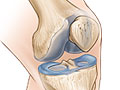

cartilage of your joints. This cushioning tissue is firm, thick, and slippery.

It covers and

protects the ends of bones where they meet to form a joint. With

arthritis, there are changes in the cartilage that cause it to break down. When

it breaks down, the bones rub together and cause damage and pain. Experts

CauseOsteoarthritis occurs

when changes in

cartilage cause it to

break down and wear away.

When cartilage breaks down, the bones rub together and cause damage